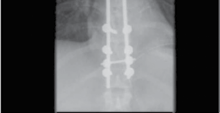

Pedicle screw instrumentation forms the biomechanical foundation of modern constructs. The freehand technique relies on precise anatomical landmarks: the intersection of the pars interarticularis, the superior articular facet, and the transverse process. The cortex is burred, and a pedicle probe is advanced with tactile feedback to ensure an intraosseous trajectory. The tract is then palpated with a ball-tipped probe to confirm five intact bony walls (medial, lateral, superior, inferior, and anterior). Alternatively, stereotactic navigation and robotic-assisted placement are increasingly utilized, particularly in cases of severe rotational deformity, revision surgery with obscured landmarks, or minimally invasive (MIS) approaches. These technologies significantly enhance the accuracy of screw placement, reducing the risk of neurological injury and biomechanical failure.

Posterior instrumentation allows for robust fixation to the pelvis, which is a massive advantage—and often a strict requirement—in long fusions in the elderly, patients with severe sagittal imbalance, and non-walking patients with neuromuscular-type curves. Stopping a long construct at L5 is associated with unacceptably high rates of L5-S1 disc degeneration, pseudarthrosis, and hardware failure. Pelvic fixation is most commonly achieved using S2-Alar-Iliac (S2AI) screws or traditional iliac screws. S2AI screws offer the advantage of remaining in line with the lumbar construct, eliminating the need for bulky offset connectors and reducing implant prominence, which is particularly beneficial in thin, malnourished patients.

Clinical & Radiographic Imaging Archive